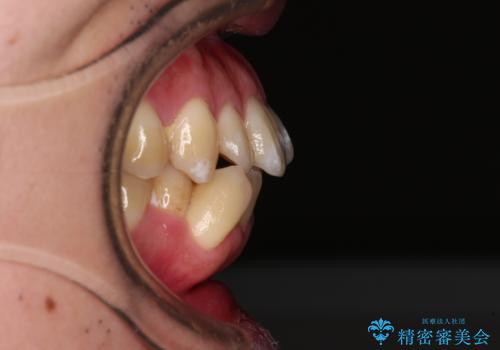

- 口が閉じられないとのことで来院された患者様です。

顎先に力を入れないと唇が閉じきれない口元であったので、上下左右の第一小臼歯4本を抜歯して、ワイヤー装置にて矯正治療を行うこととしました。